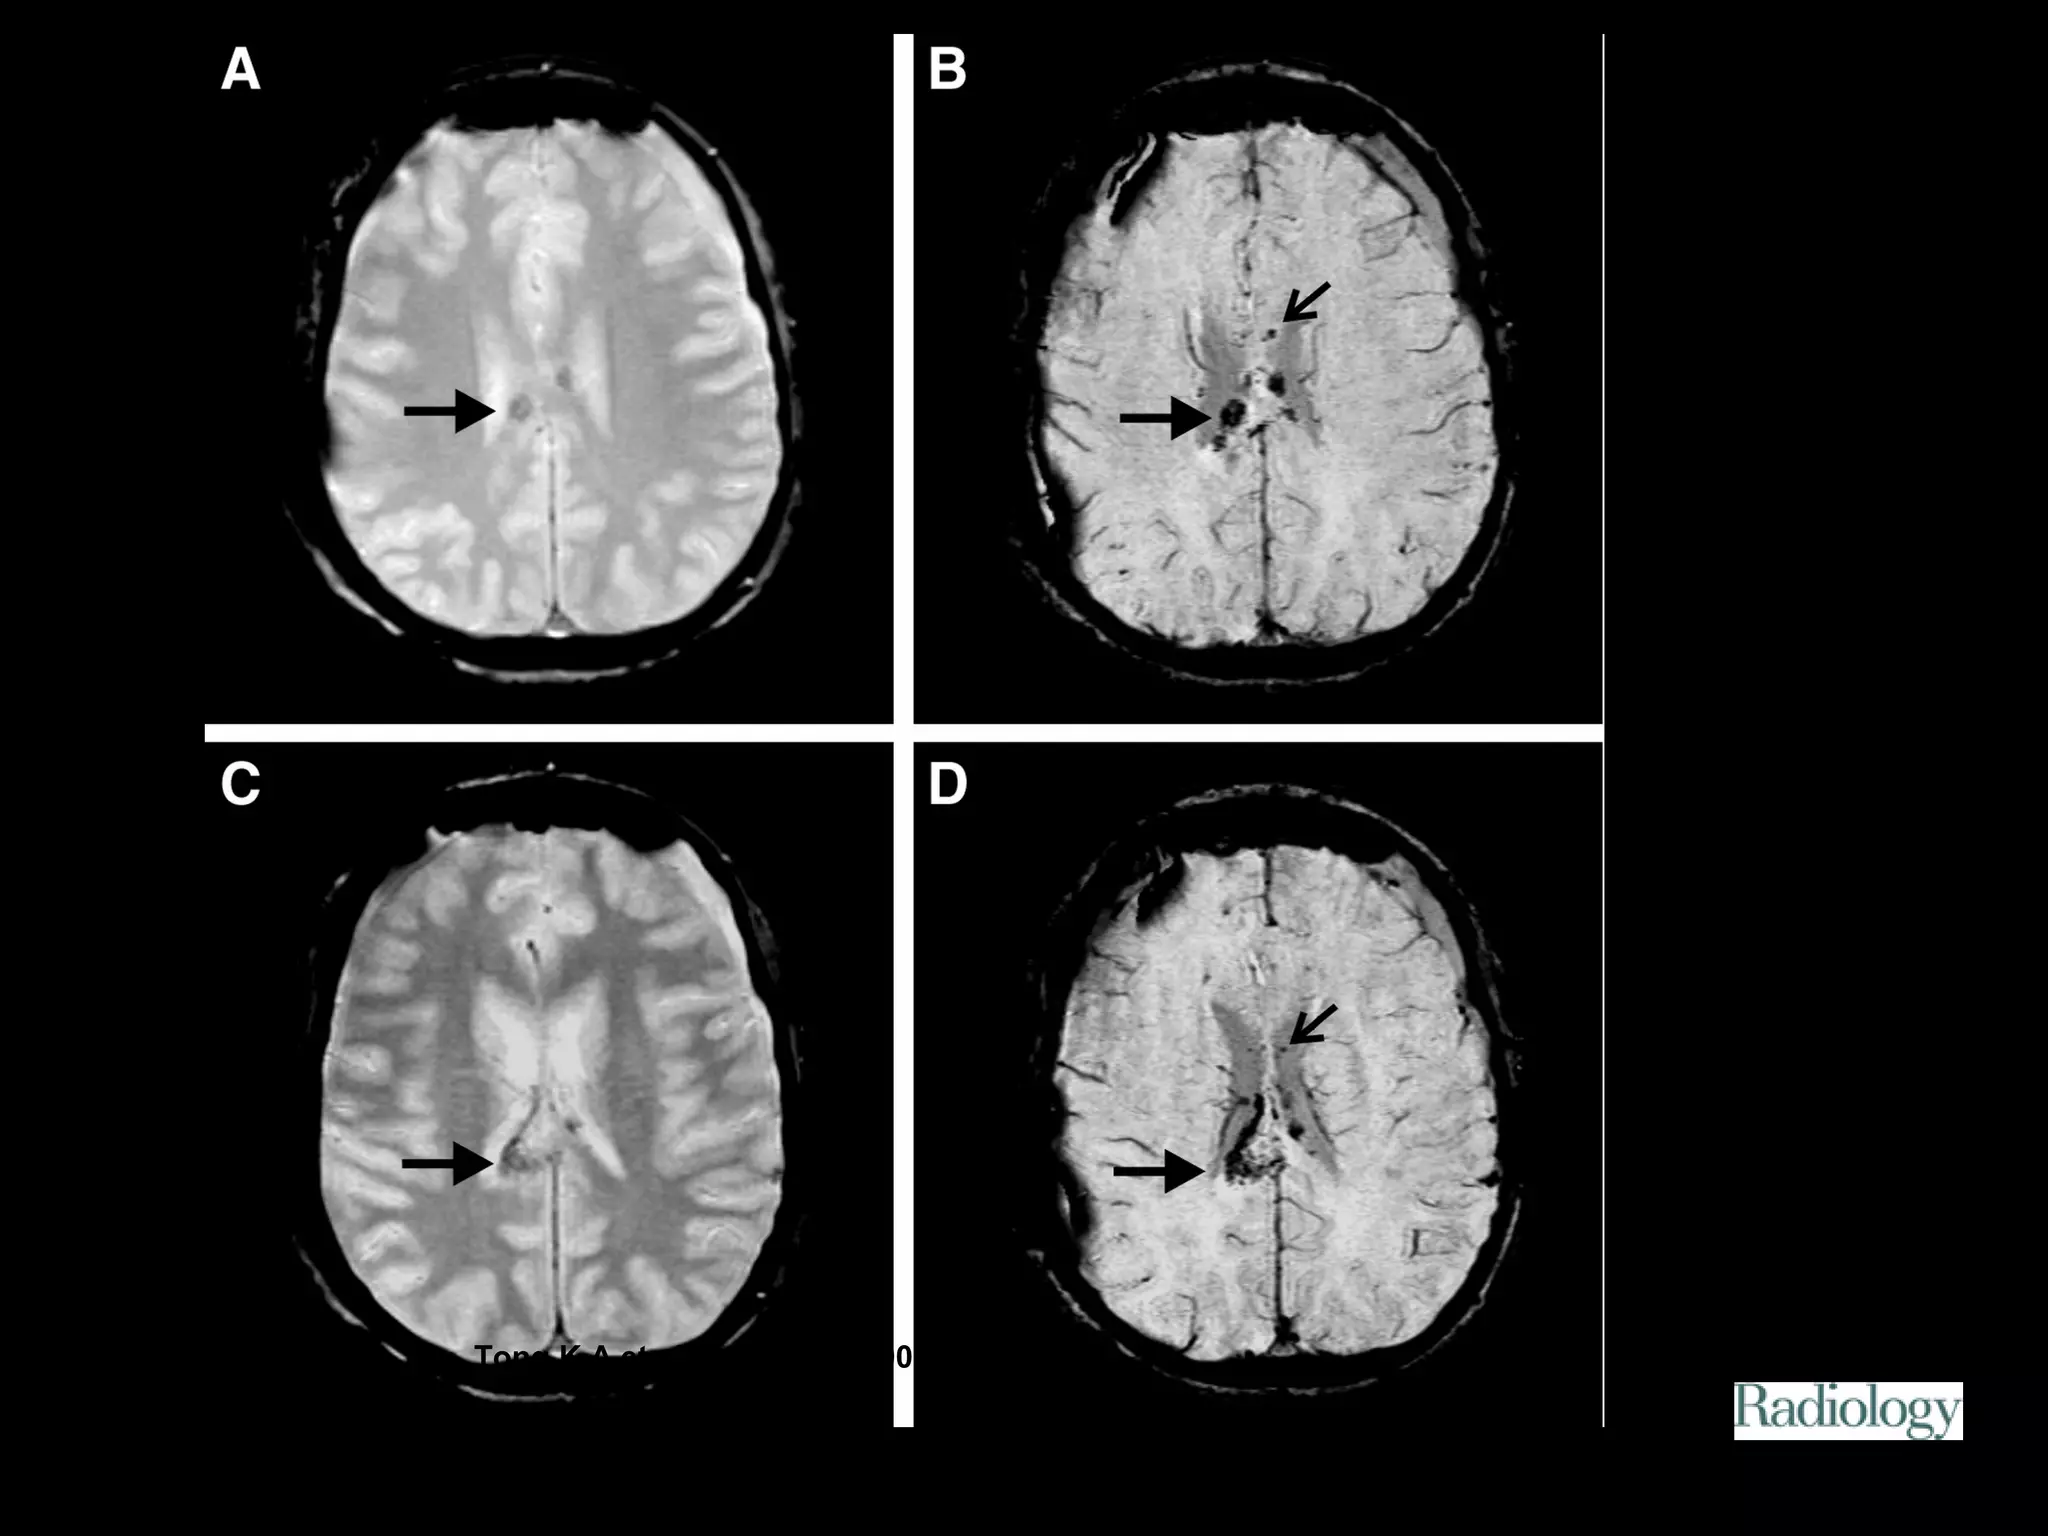

Figure 1. Patient 2.

Tong K A et al. Radiology 2003;227:332-339

©2003 by Radiological Society of North America

Figure 2. Patient 4.

Figure 3. Patient 2.

Editor's Notes

• #25 Figure 1. Patient 2. A, Transverse GRE (fast imaging with steady-state precession, 500/18, 15° flip angle, 78 Hz per pixel, two signals acquired, 4-mm-thick sections) and, B, SW (three-dimensional fast low-angle shot, 57/40, 20° flip angle, 78 Hz per pixel, 32 partitions, one signal acquired, 2-mm-thick sections reconstructed over 4 mm) MR images obtained in an 11-year-old boy who was injured in a motor vehicle accident. Small hemorrhagic shearing injuries (arrows in B), such as those commonly seen in the subcortical junction of gray and white matter, were often seen only on the SW MR images.

• #26 Figure 2. Patient 4. A, C, Transverse GRE MR images (fast imaging with steady-state precession, 500/18, 15° flip angle, 78 Hz per pixel, two signals acquired, 4-mm-thick sections) obtained at two different levels of the corpus callosum in a 14-year-old girl who was injured in a motor vehicle accident. B, D, Corresponding transverse SW MR images (three-dimensional fast low-angle shot, 57/40, 20° flip angle, 78 Hz per pixel, 32 partitions, one signal acquired, 2-mm-thick sections reconstructed over 4 mm) obtained in the same girl show hemorrhagic shearing lesions with variable sizes and shapes in the corpus callosum. The smallest lesions (small arrow in B and D) are seen only on the SW MR images. The larger lesions (large arrow) are more visible on the SW MR images owing to greater hypointensity and are only slightly larger on these images than on the GRE MR images.

• #27 Figure 3. Patient 2. A, Transverse GRE (fast imaging with steady-state precession, 500/18, 15° flip angle, 78 Hz per pixel, two signals acquired, 4-mm-thick sections) and, B, transverse SW (three-dimensional fast low-angle shot, 57/40, 20° flip angle, 78 Hz per pixel, 32 partitions, one signal acquired, 2-mm-thick sections reconstructed over 4 mm) MR images obtained in an 11-year-old boy who was injured in a motor vehicle accident. Brain stem lesions (small arrow) often were either poorly visualized or invisible on the GRE images compared with their appearance on the SW MR images. The mild increase in blooming artifact (large arrow) on the SW MR images also accentuates the magnetic susceptibility effects from the bones of the skull base.